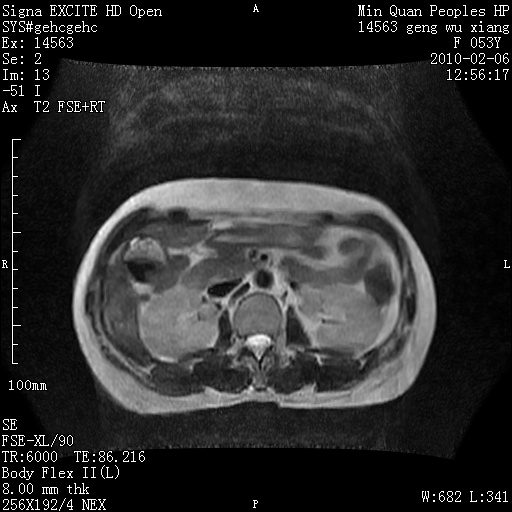

标题: MRI2762:胆道梗阻原因?

f,53y,全身黄染多日。

高位胆道梗阻 胆管癌可能性大

支持 高位胆道梗阻 胆管癌可能性大。